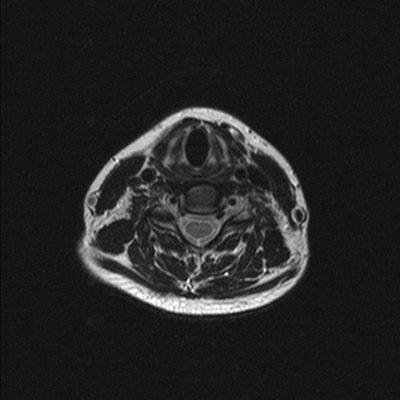

МРТ шеи: оценка спинного мозга (сагиттальная плоскость, Т2 последовательность)

МРТ шейного отдела позвоночника - высокоинформативный неинвазивный способ диагностики, использующий магнитное поле и компьютерную обработку для получения изображений. Преимущества магнитно-резонансного сканирования в сравнении с рентгеновскими методами обследования - отсутствие лучевого воздействия и возможность детализации патологических процессов в мягких тканях: на томограммах видны хрящи, синовии, связки, межпозвонковые диски, спинной мозг, нервы. Если в организме человека нет металлических составляющих или функционирующих устройств с ферромагнитными свойствами, негативные последствия, включая отдаленные, после проведения диагностической процедуры отсутствуют.